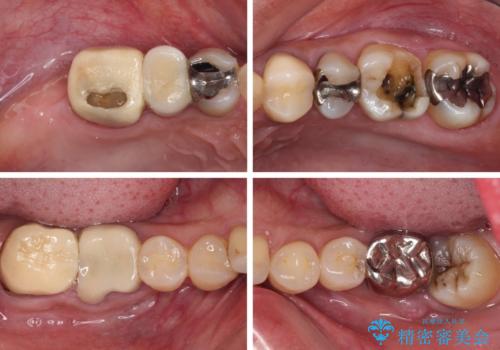

- 奥歯を治療しようと他院で開始したものの、放置してしまったとのことで来院された患者様です。

外れてしまった銀歯や穴の空いた仮歯などあり、適合の悪い被せものと合わせて、セラミッククラウンやセラミックインレーにて治療と行うこととしました。